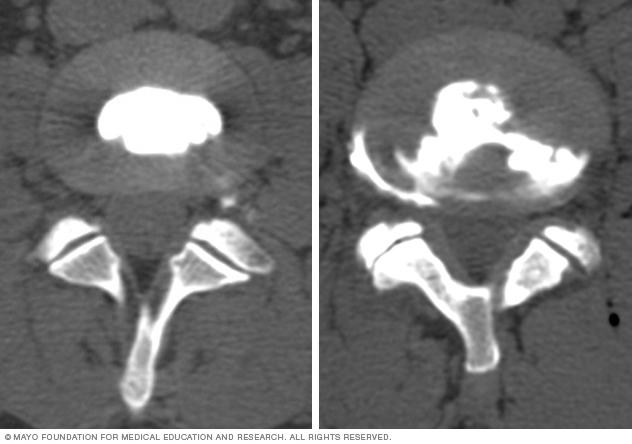

Images comparing how dye looks in normal and damaged spinal disks.

If the dye stays in the center of the disk, the disk is not damaged. If the dye spreads outside the center of the disk, the disk has undergone wear-and-tear change, which may or may not be painful.

If the dye stays in the center of the disk, the disk is not damaged. If the dye spreads outside the center of the disk, the disk has undergone some wear-and-tear change. The change might or might not be the cause of your pain.